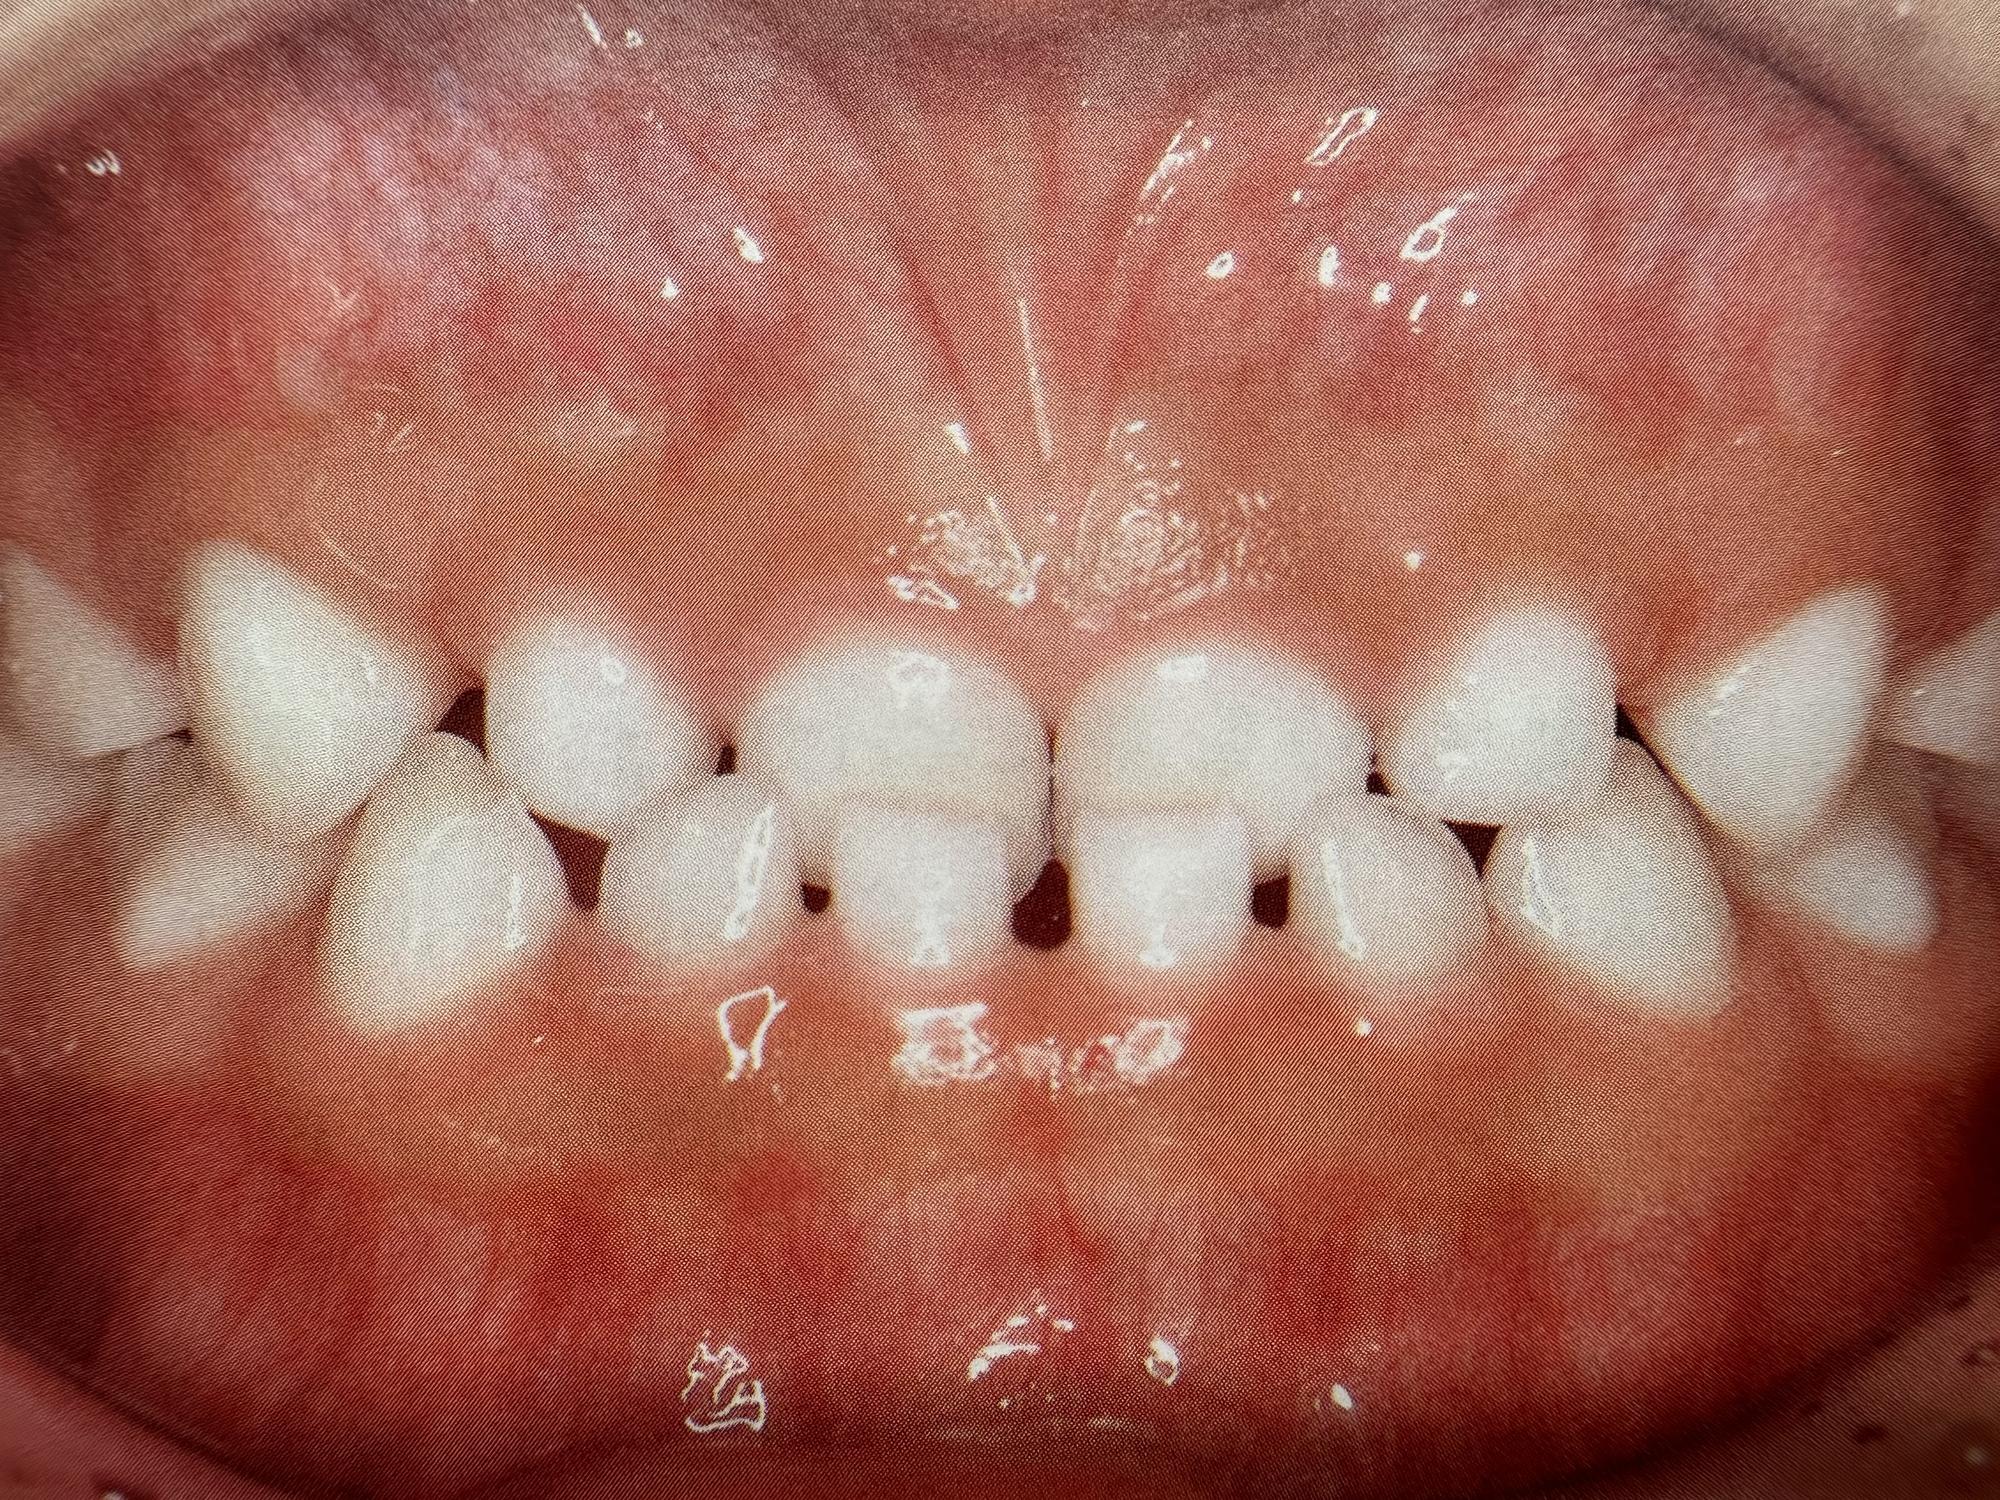

反対咬合とは、本来は上の前歯が前に出ているべきところ、逆に下の前歯が前に出てしまっている噛み合わせのことを指します。

人によっては顎全体が前に出ているように見えるため、横顔のシルエットにも特徴が出やすい噛み合わせです。乳歯の段階で軽い反対咬合に見える場合もありますが、成長とともに顎の骨のバランスが強く影響してくると、自然に治るケースは限られてきます。